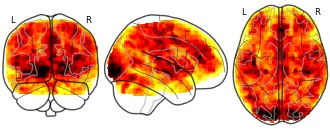

License information was derived automaticallyDescriptionGroup mean on contrast Reliving memories compared to Reading memories for the people with borderline personality disorder (BPD)

This dataset contains data on a task in which participants relive autobiographical memories (RAM task) collected during the research project titled: “Social Feedback and Emotion Regulation in Borderline Personality Disorder: An fMRI study”. The goal of this substudy was to elucidate the mechanisms underlying positive memory reliving with emphasis on memory vividness and areas relevant to autonoetic consciousness, and how this may benefit mood and state self-esteem for people with Borderline Personality Disorder. Participants relived four neutral and four positive memories in an MRI scanner while rating mood and vividness.

Modality

fMRI-BOLD

Cognitive paradigm (task)

autobiographical memory task

Map type